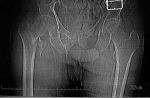

【新技术】我院骨二科采用肩关节置换技术治疗肱骨近端粉碎性骨折

图一:手术术前片可见左侧肱骨近端粉碎性骨折、肱骨头脱位、难以行骨折内固定图二:手术术后复查可见假体安放位置良好肱骨近端骨折多发生于老年人群,对于复杂的近端粉碎骨折患者,骨折复位钢板内固定手术术后骨折不愈合、延迟愈合甚至肱骨头坏死发生率较高。...